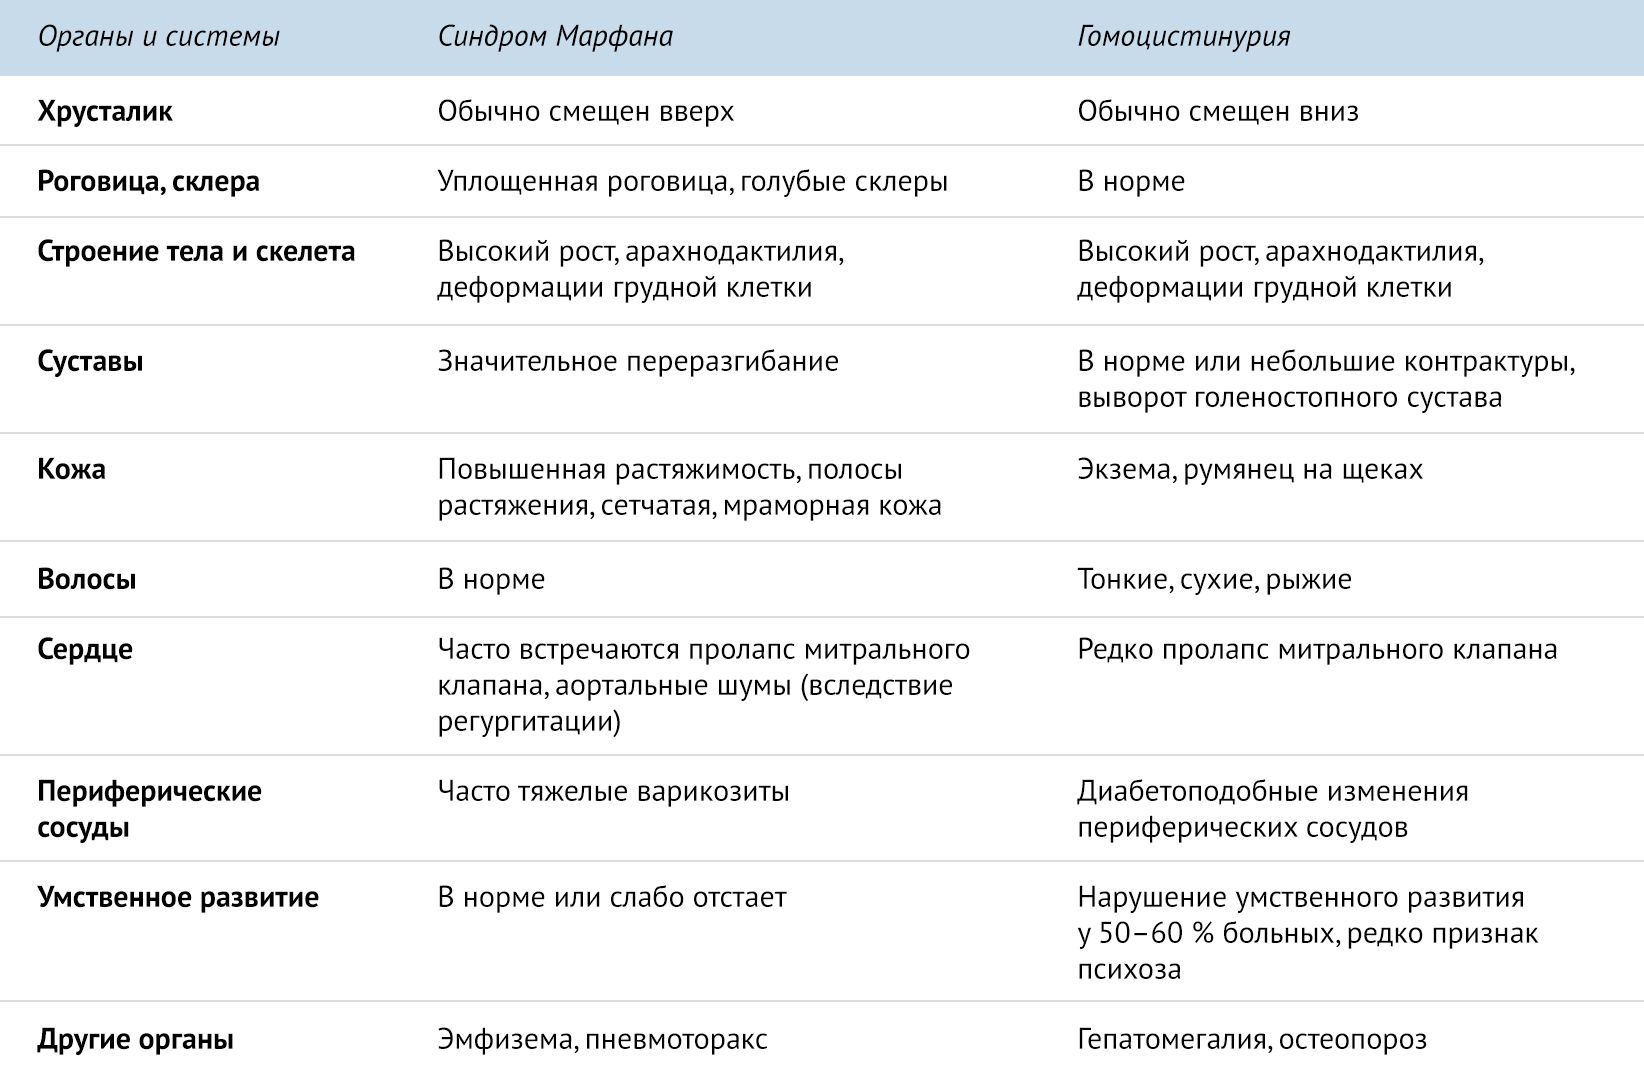

Sindrom Marfana Tema Nauchnoj Stati Po Klinicheskoj Medicine Chitajte Besplatno Tekst Nauchno Issledovatelskoj Raboty V Elektronnoj Biblioteke Kiberleninka

Neonatalnaya Forma Sindroma Marfana Klinicheskoe Opisanie I Kompleksnyj Podhod K Diagnostike I Lecheniyu Tema Nauchnoj Stati Po Klinicheskoj Medicine Chitajte Besplatno Tekst Nauchno Issledovatelskoj Raboty V Elektronnoj Biblioteke Kiberleninka

Neonatalnaya Forma Sindroma Marfana Klinicheskoe Opisanie I Kompleksnyj Podhod K Diagnostike I Lecheniyu Tema Nauchnoj Stati Po Klinicheskoj Medicine Chitajte Besplatno Tekst Nauchno Issledovatelskoj Raboty V Elektronnoj Biblioteke Kiberleninka

Sindrom Marfana Tema Nauchnoj Stati Po Klinicheskoj Medicine Chitajte Besplatno Tekst Nauchno Issledovatelskoj Raboty V Elektronnoj Biblioteke Kiberleninka